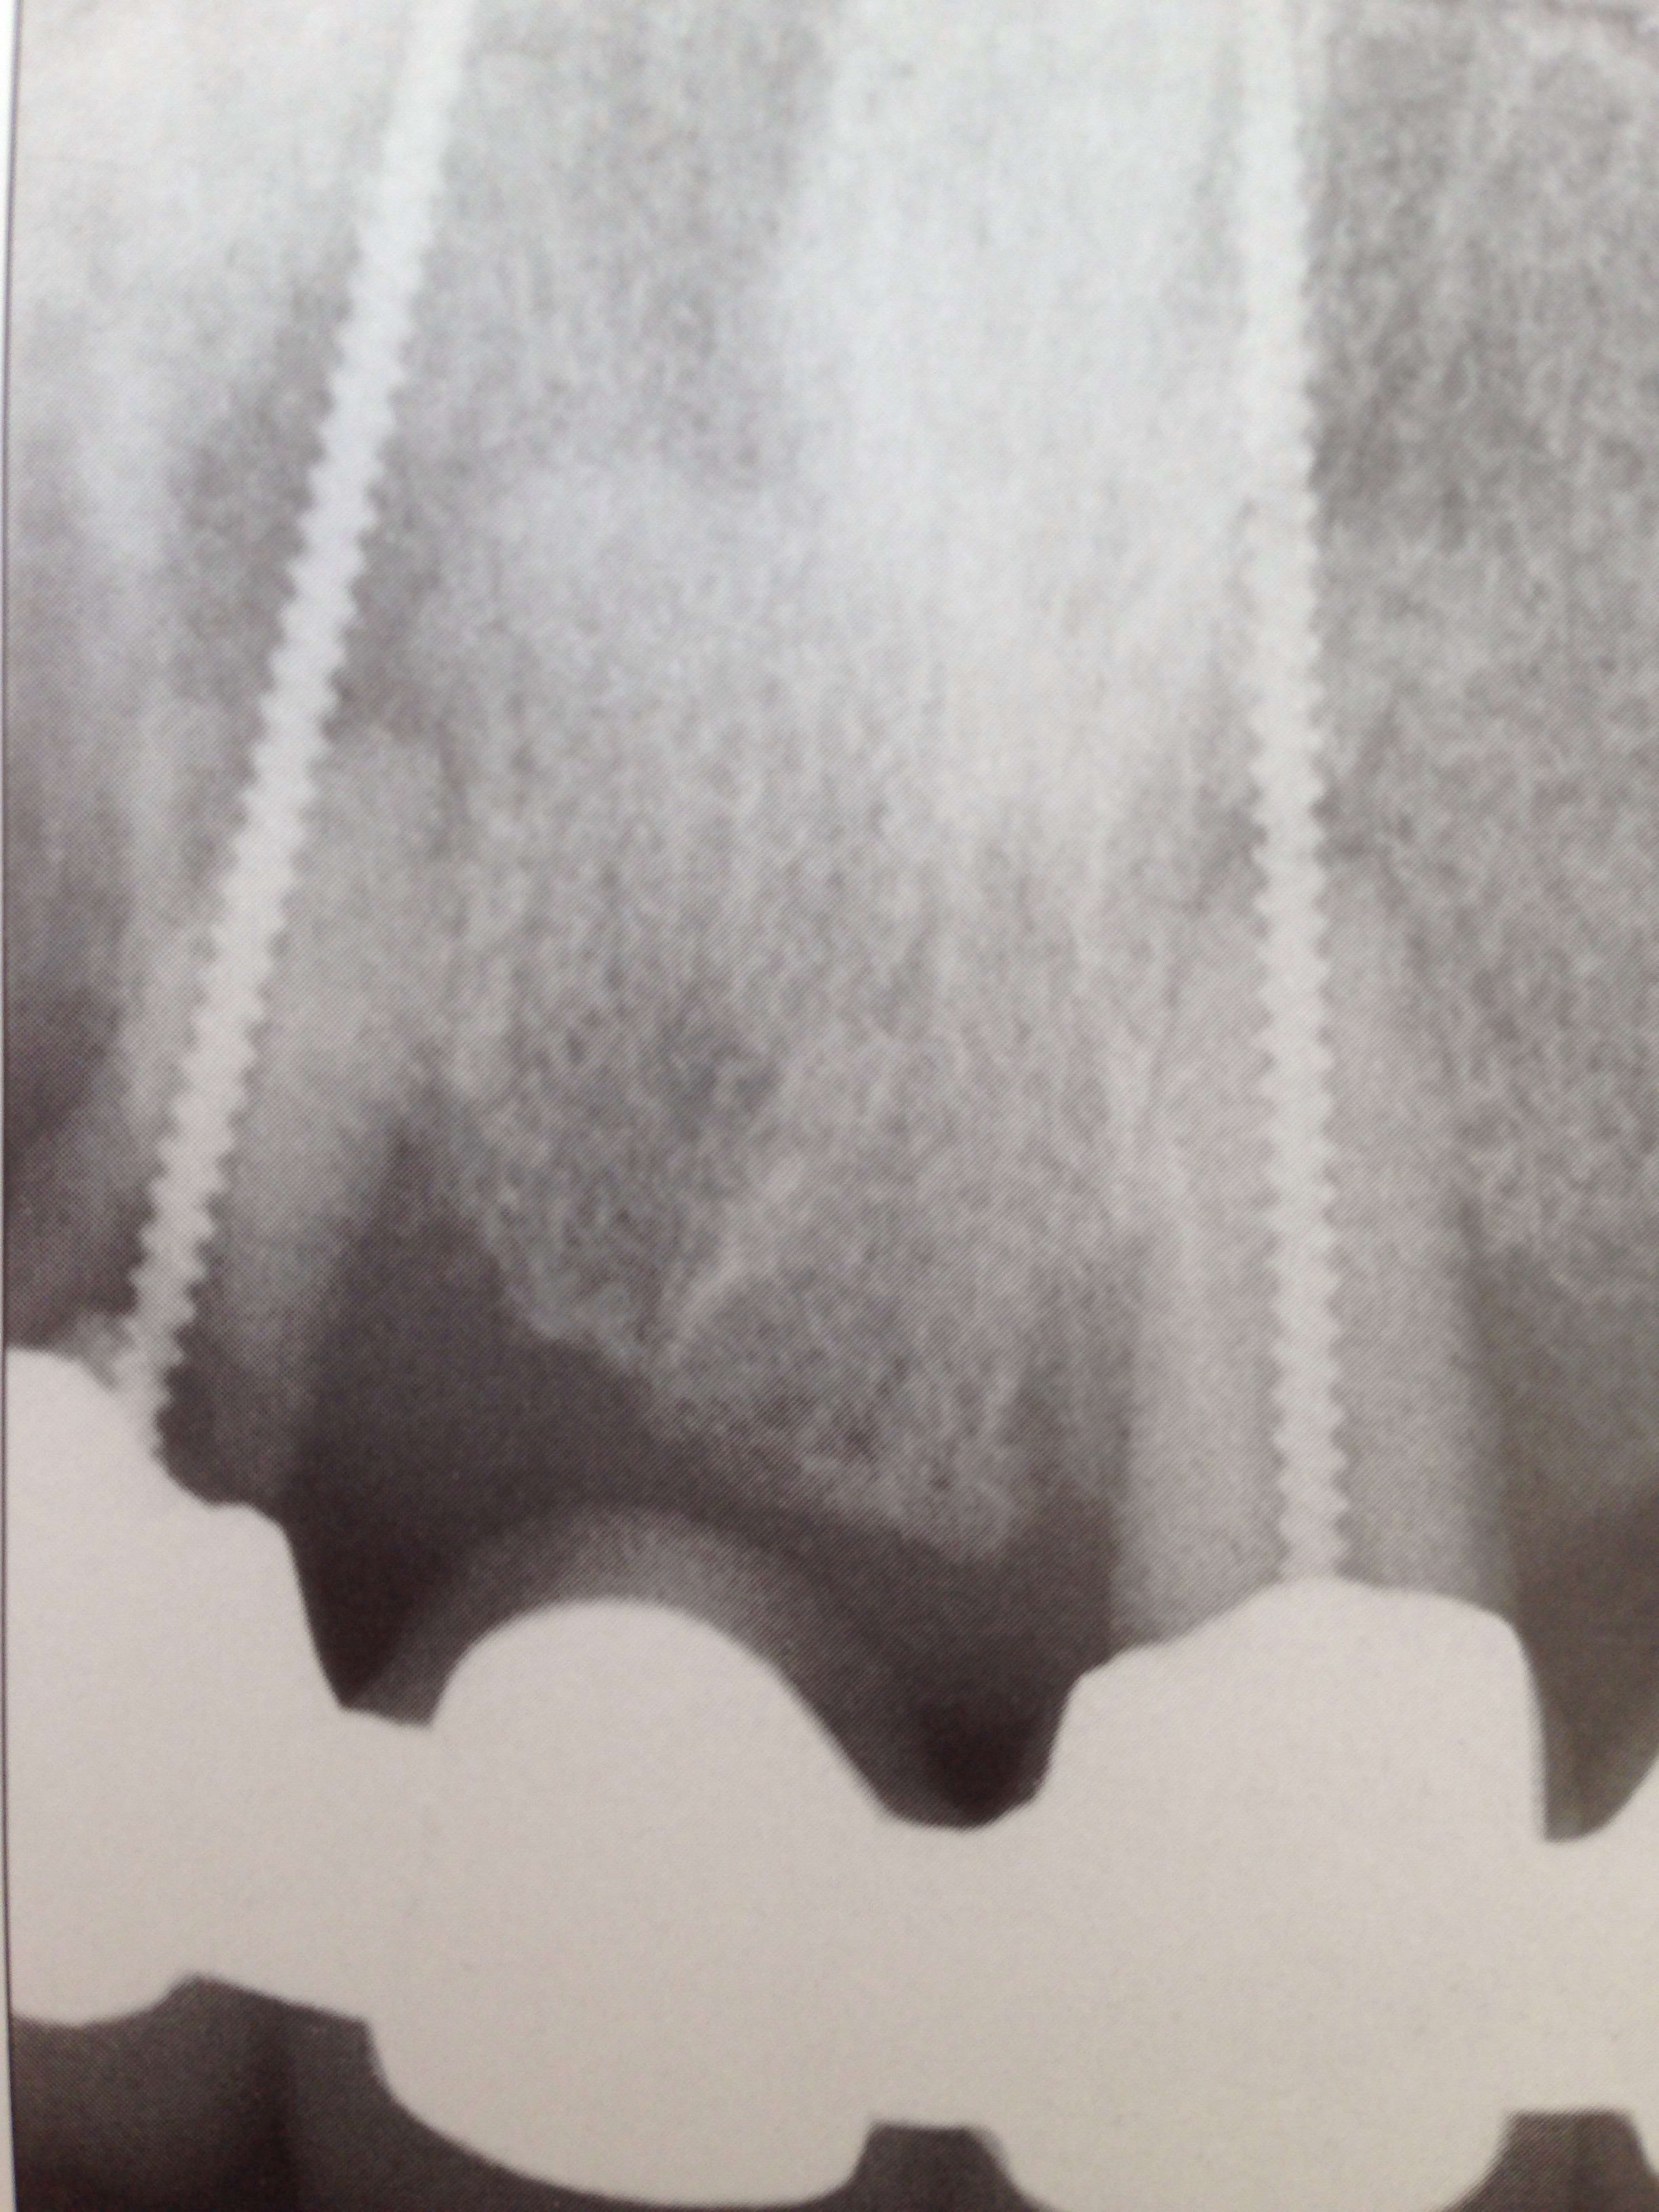

- Implant linkow

- implant aiguille

De la pano la moins marrante Ă  la plus marrante :